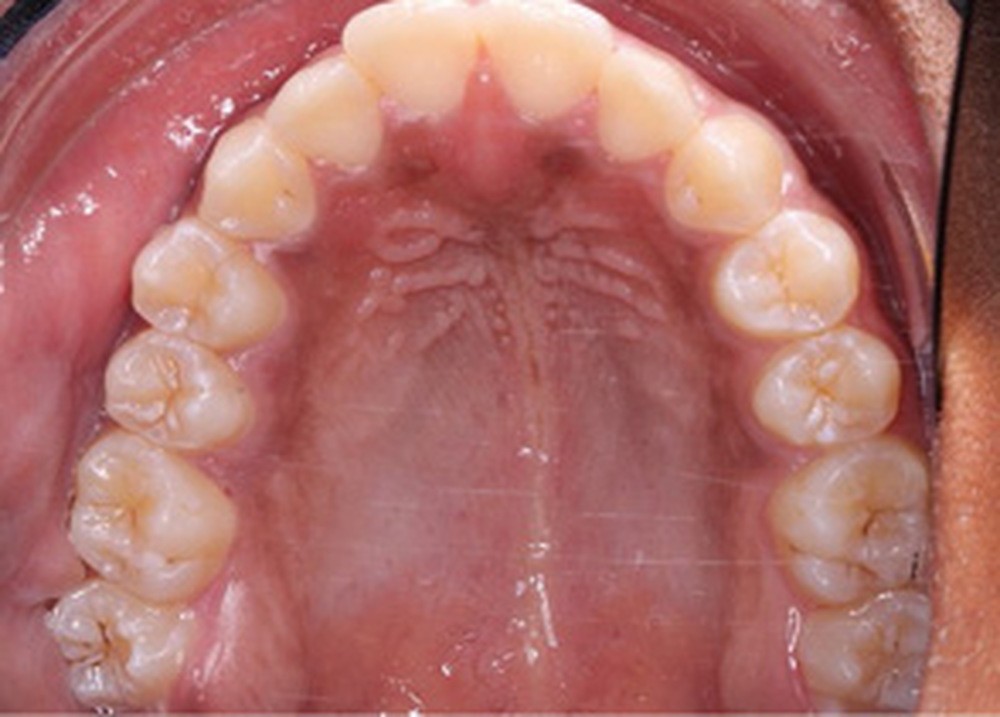

Examen clinique (fig. 1a-h)

L’examen clinique endo-buccal révèle une denture adulte jeune avec un inversé d’articulé antérieur de 13 à 23, des tatouages gingivaux ethniques et des taches de décalcifications, un parodonte sain mais un brossage insuffisant.

L’arcade maxillaire est en V et la voûte palatine profonde. L’arcade mandibulaire a une forme en U (non-concordance des formes d’arcade) et présente des malpositions des dents cuspidées. La médiane mandibulaire est décalée à gauche de 2 mm ; le recouvrement antérieur est de 2 mm ; les molaires sont en classe III avec un surplomb inversé.